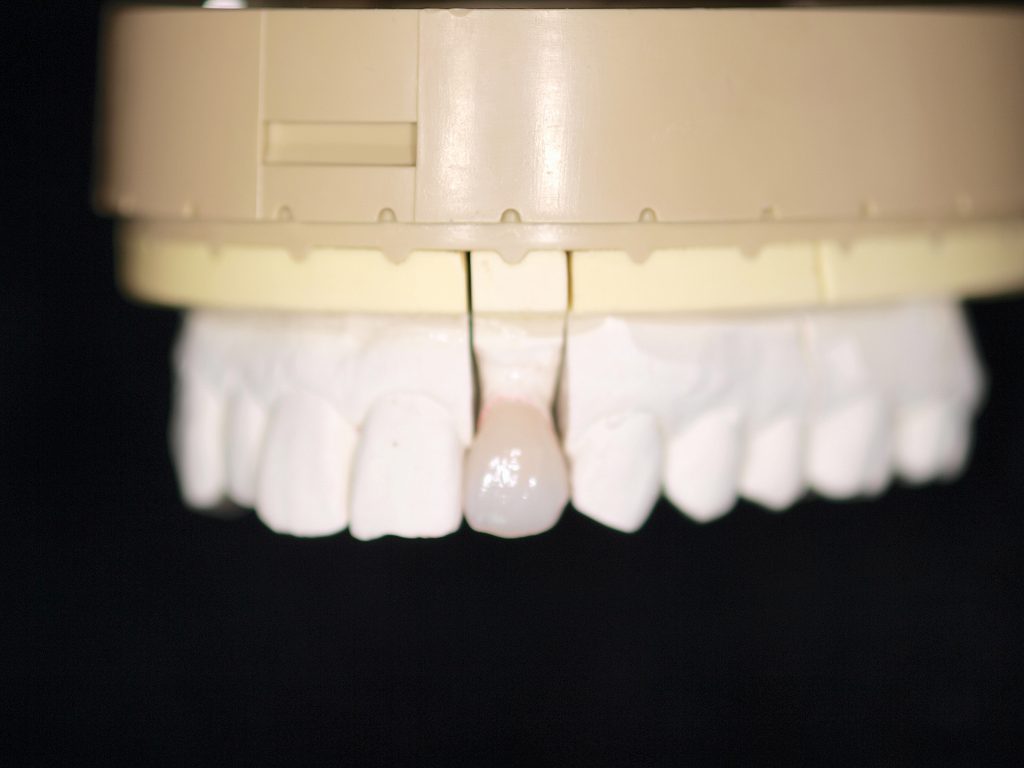

前歯部の作成はジルコニアフレームを使ったジルコニアクラウンというやり方とe-maxを使ったオールセラミッククラウンというやり方に分かれます。 強度はジルコニアフレームの方がありますが、複雑な工程を要しますので費用は2万円高く8万円となります。

前歯部の作成はジルコニアフレームを使ったジルコニアクラウンというやり方とe-maxを使ったオールセラミッククラウンというやり方に分かれます。 強度はジルコニアフレームの方がありますが、複雑な工程を要しますので費用は2万円高く8万円となります。